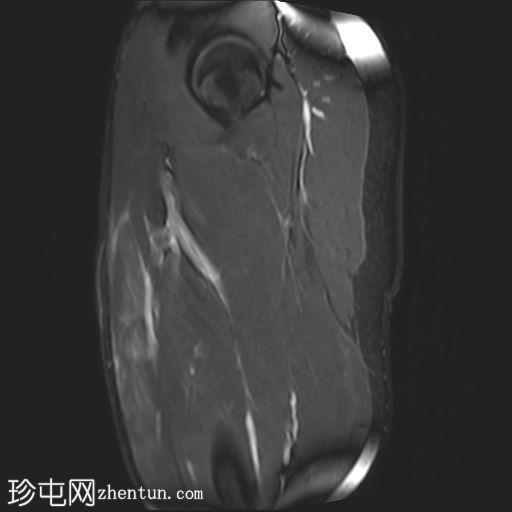

矢状位

T1加权像

左侧股直肌近端肌腱交界处可见异常高信号,向远端延伸约至肌长一半。

可见清晰的充满液体的分离平面,呈“靶心征”,将双羽状间接头与浅表单羽状直接头分隔开,呈现出股直肌脱套样损伤的特征性影像

间接头肌纤维与近端肌腱保持连续,未见肌腱断裂或明显回缩。

可见轻度肌间及筋膜周围水肿。病例讨论